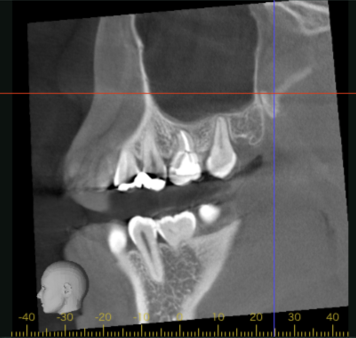

初診時CT画像

初診時デンタルX線写真とCT画像。

根管外に不透過像とそれを取り囲む透過像を認める。

コアを除去すると、分岐部へつながるパーフォレーションを認めた。

これが排膿の原因であったため、保存は困難と判断した。